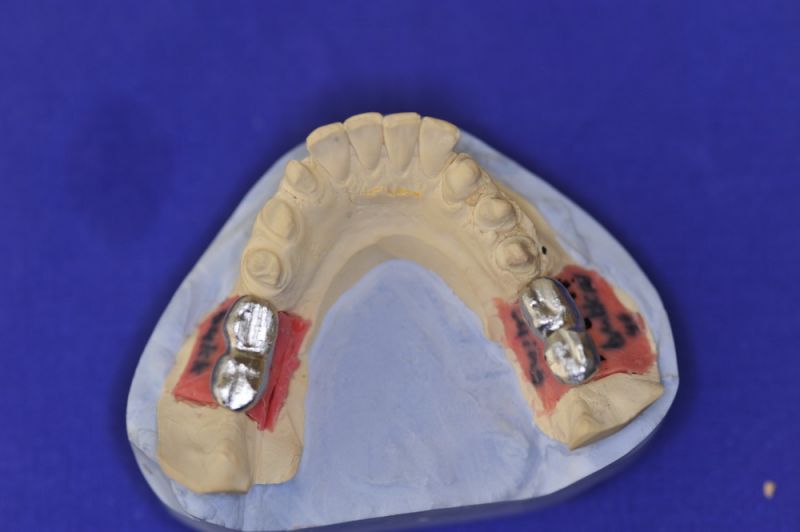

Neuromuskulär zentrierte Bisslage. Gerüste werden unbelastet durch das "Zahnfleisch" nach oben gehoben

Nun stellte sich heraus, dass der Abstand zwischen den Implantaten sehr gering war, weil die Einschubrichtungen der Aufbauten sich zum Teil gegenseitig im Wege standen. Konfektionierte Teile mussten individuell umgeschliffen werden, dabei das Ziel, den Biss korrekt einzustellen nicht aus dem Auge zu verlieren.

Heute war nun Gerüsteinprobe, mit all den Problemen der Umsetzung zwischen Laborsituation und Mundsituation. Siehe Stichpunkt "Schnittstellenproblematik"! was bei Zähnen, auf Grund deren Eigenbeweglichkeit im Kieferkochen kein Problem wäre, ist bei drei unbeweglichen Implantaten ein Riesenproblem. Darüber spricht nur in aller Regel Niemand! Es musste viel fein nachgearbeitet werden.